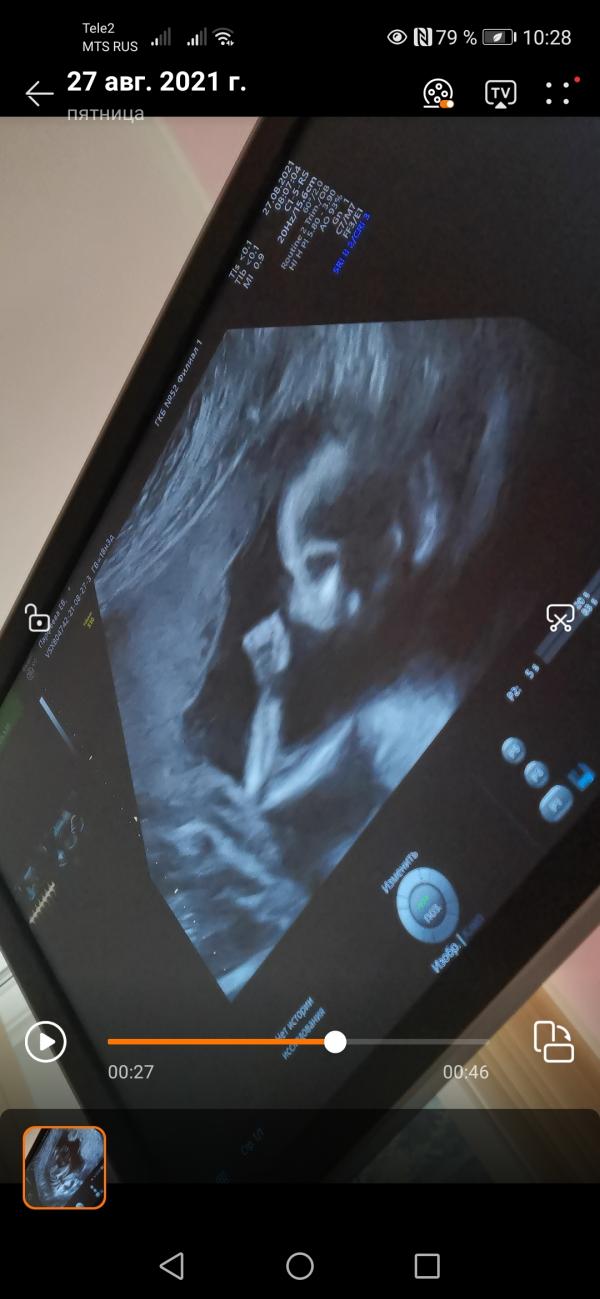

2й скрининг)).

Пришла сегодня 18.5 по месячным и 18.3 по первому скринингу). Я спрашивала у врача в жк не рано ли она меня записала, она сказала в самый раз. 🙈

Так вот мы с сыном подготовились, приехали на 30 минут раньше гуляли кругами вокруг больницы, съели пирожок из макдака и гляссе выпили)) на 1м скрининге просто 3 часа будила ребенка и с 4го раза только смогли все посмотреть, поэтому тут подготовились).